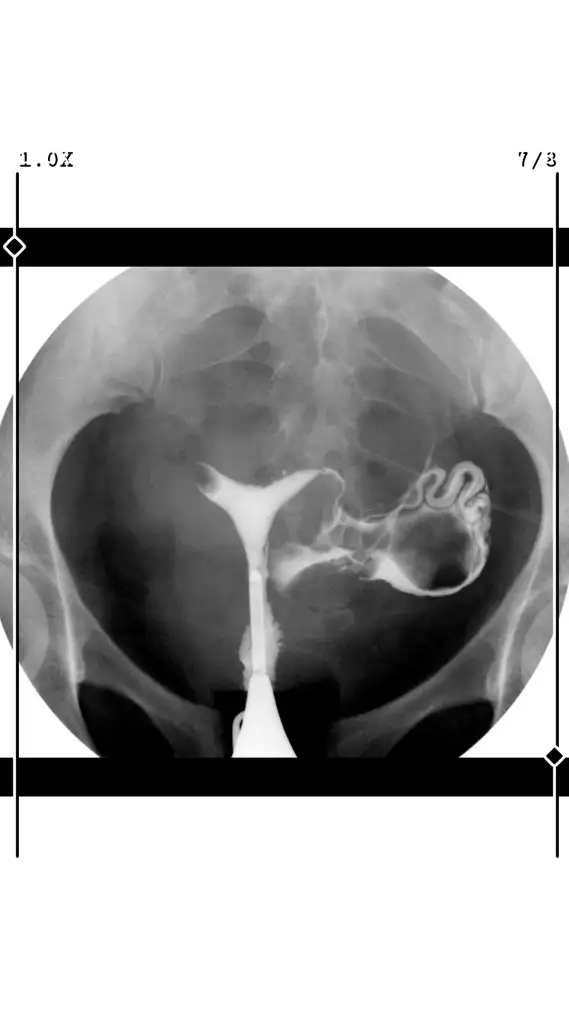

Acil rahim filmi yorumlarmisiniz